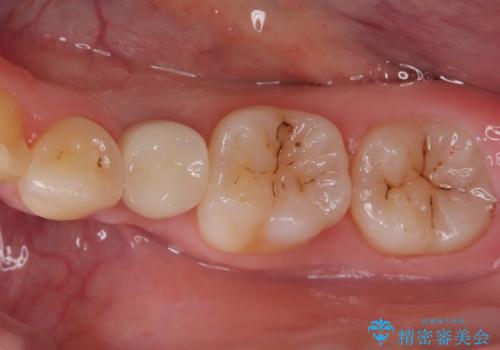

小臼歯のインプラント

- 小臼歯が先天性欠損していたため、インプラントにて補綴しています。

当院ではストローマンインプラントを導入しています。